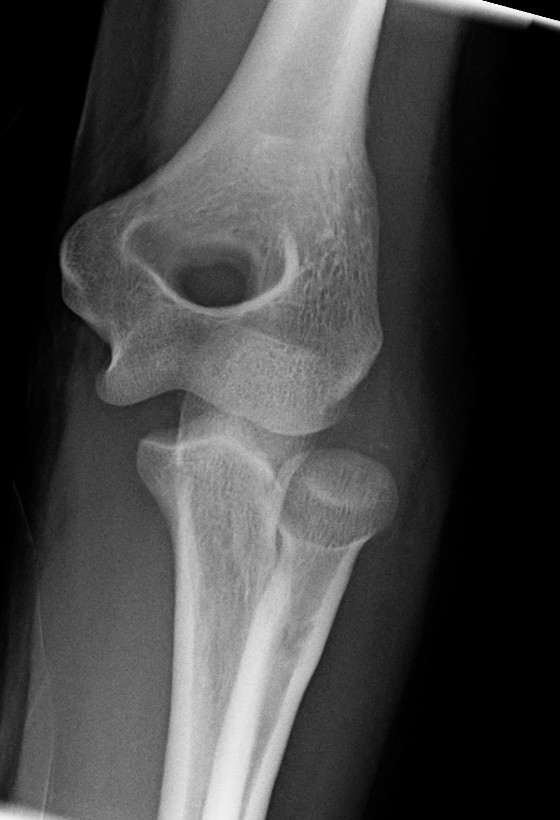

팔꿉관절(주관절)은 상완골, 요골, 척골 사이에 존재하는 관절이다. 굽힘과 폄(굴신)을 행하는 것은 주로 위팔뼈와 척골 사이이다.

팔꿈치 관절은 공통 관절낭으로 둘러싸인 세 개의 다른 부분으로 구성되어 있다. 이들은 상완의 상완골, 전완의 요골와 척골 사이의 관절이다.| 관절 | 에서 | 로 | 설명 |

| 상완척골 관절 | 자뼈의 도르래절흔 | 상완골의 도르래 | 단순한 경첩 관절로 굴곡 및 신전 운동만 가능하다. |

| 상완요골 관절 | 요골 머리 | 상완골의 작은머리 | 볼 소켓 관절이다. |

| 근위 요척 관절 | 요골 머리 | 자뼈의 요골절흔 | 굴곡 또는 신전의 모든 위치에서 요골은 손을 함께 운반하며 회전할 수 있다. 이 움직임에는 손바닥 엎침과 손바닥 뒤침이 포함된다. |

해부학적 자세에서 팔꿈치에는 네 개의 주요 뼈대 랜드마크가 있다. 상완골의 하단에는 몸에 가장 가까운 쪽(내측)과 몸에서 가장 먼 쪽(외측) 표면에 있는 상완골 내측 상과와 상완골 외측 상과가 있다. 세 번째 랜드마크는 자뼈 머리에서 발견되는 주두이다. 이들은 ''Hueter 선''이라고 하는 수평선상에 놓여 있다. 팔꿈치가 굴곡될 때, 이들은 정삼각형과 유사한 ''Hueter 삼각형''이라고 하는 삼각형을 형성한다.[5]